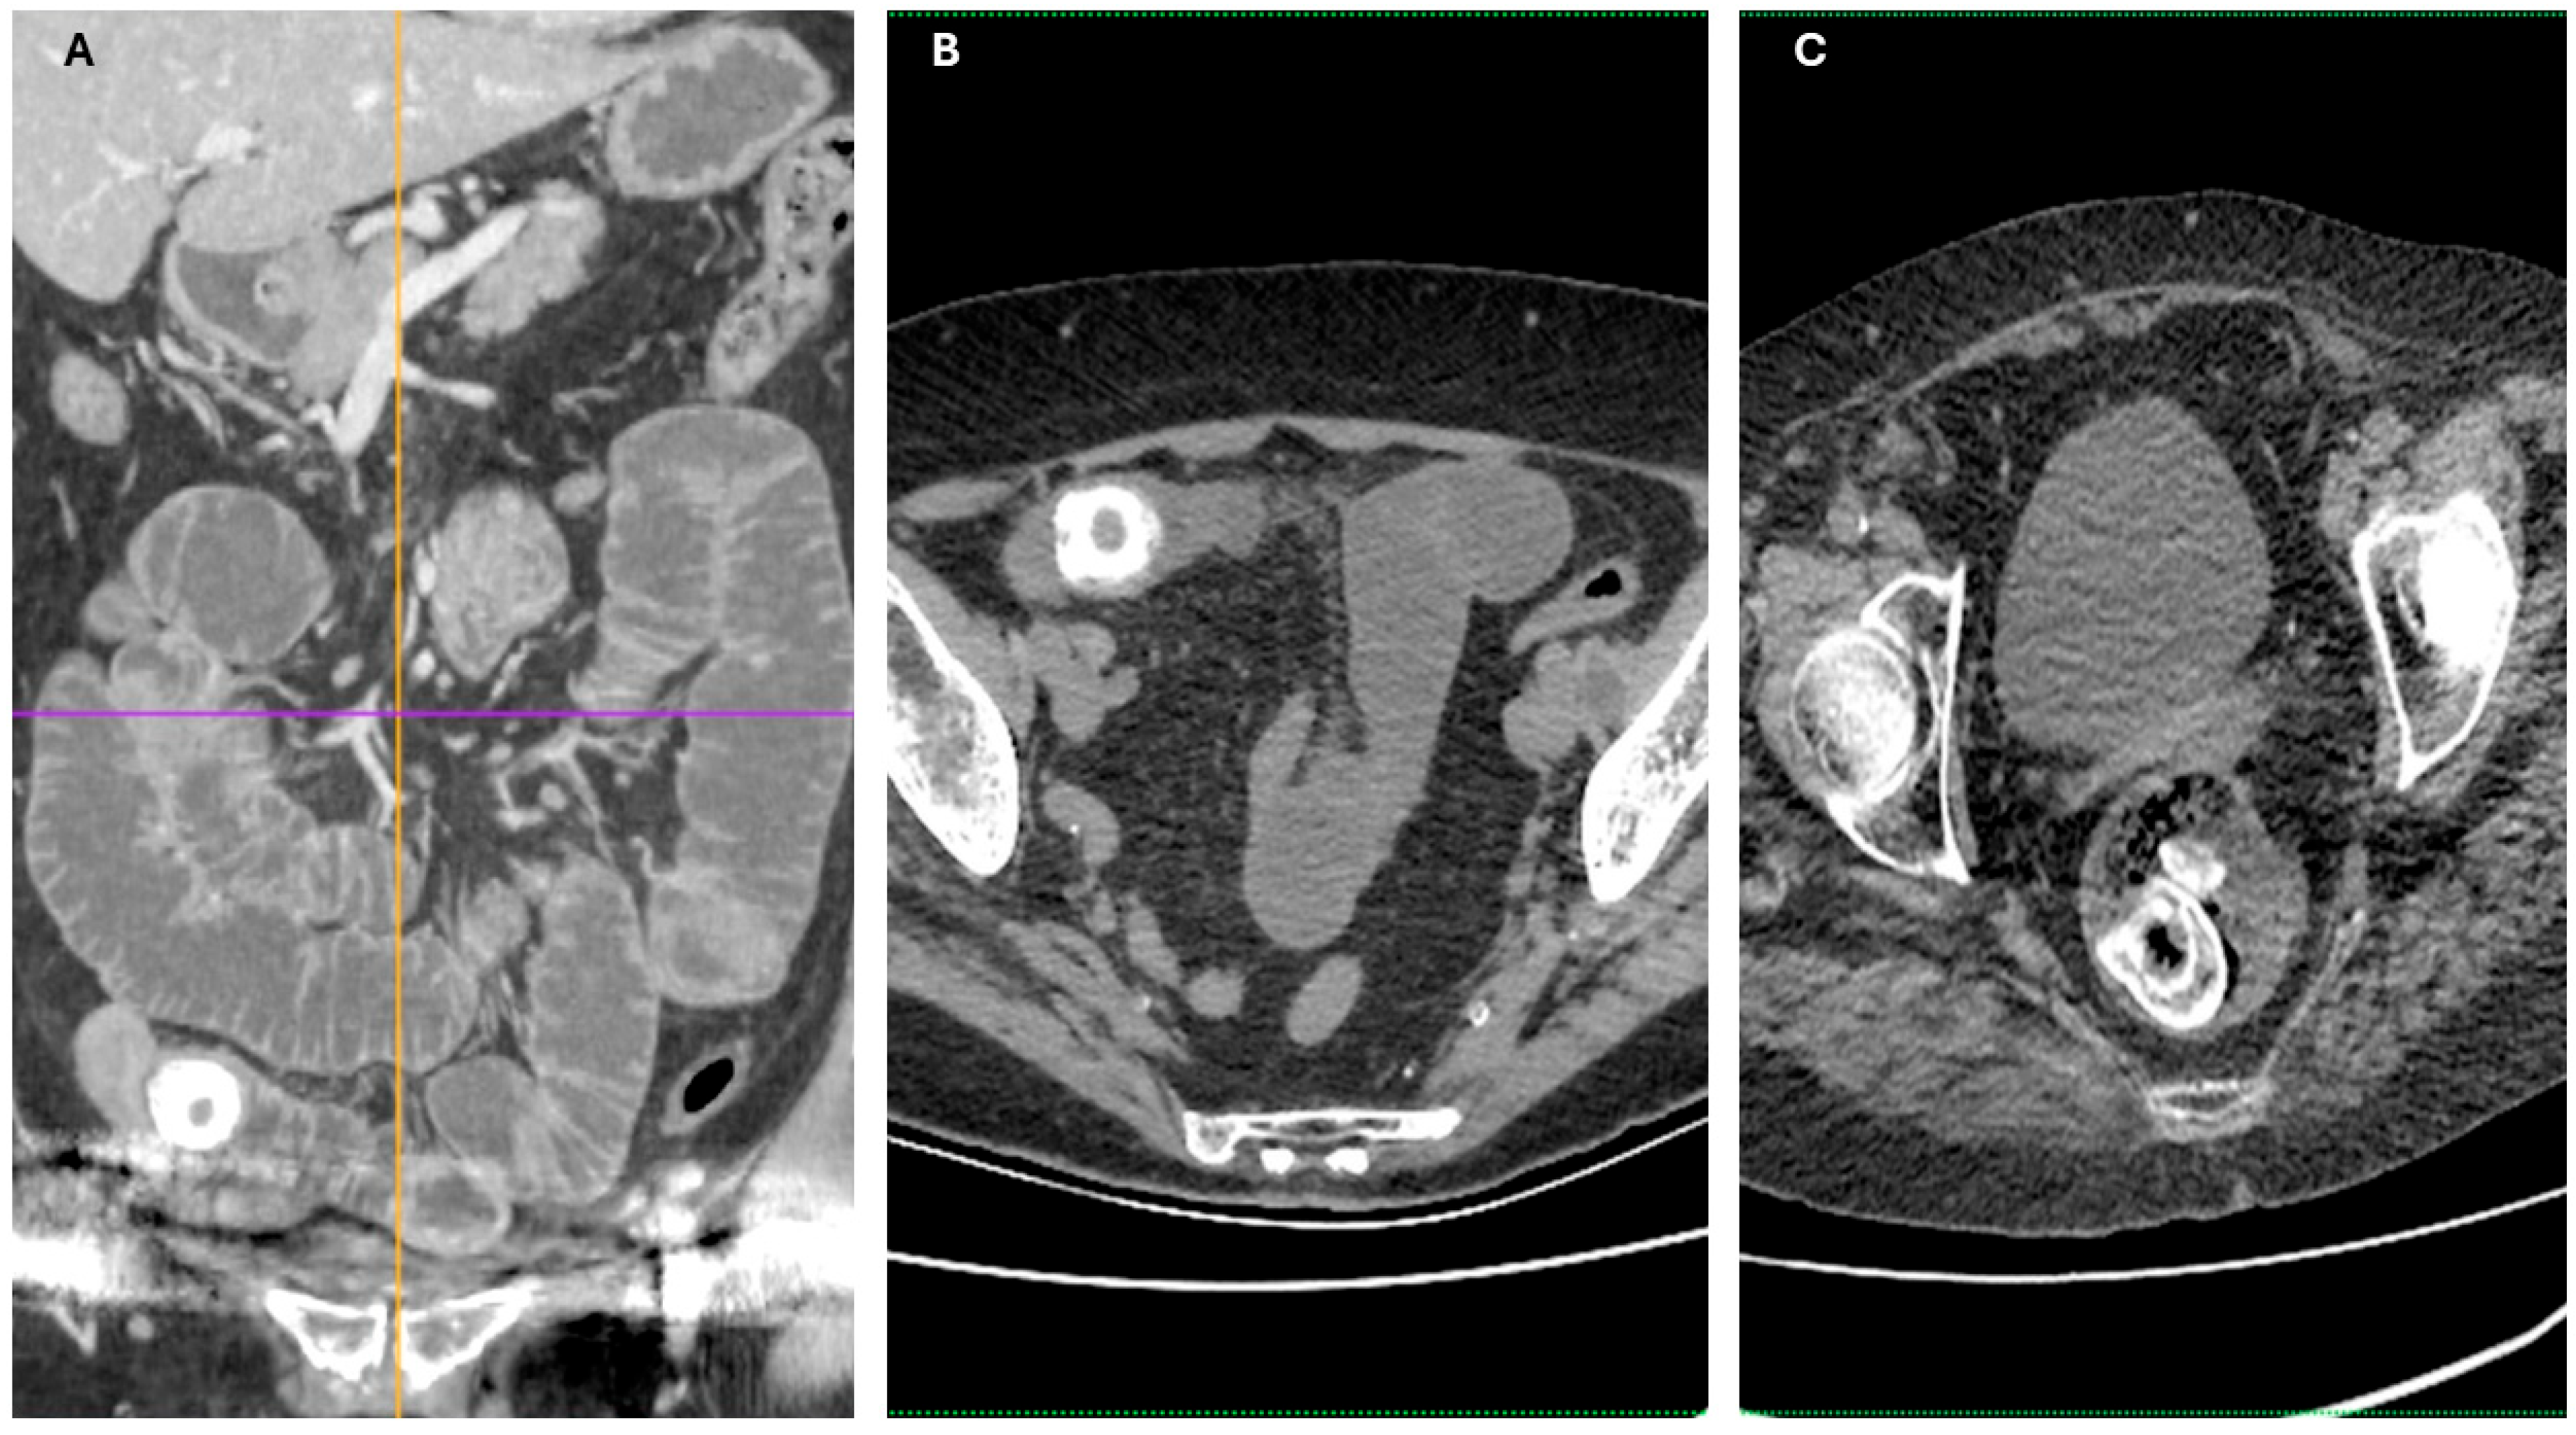

Imaging findings were consistent with biliary ileus, characterized by the presence of ectopic gallstones within the gastrointestinal tract. As shown in Figure 3A–C, axial and coronal CT images demonstrated radiopaque enteric gallstones. Figure 4 highlights a gallstone associated with a cholecystoduodenal fistula. Further axial and coronal sections (Figure 5A–C) show additional enteric gallstones, including one in the rectal ampulla.

Figure 5. Distal migration of enteric gallstones in biliary ileus. (A,B) Coronal and axial CT images depicting a highly radiopaque enteric gallstone located in the projection of the colon-biliary ileus. (C) Axial CT section showing a radiopaque enteric gallstone in the projection of the rectal ampulla, indicating distal migration—biliary ileus. Acquisition with 5 mm slice thickness and 3 mm reconstruction. Images have been cropped and zoomed for optimal visualization while maintaining the original scale; a 10 mm scale bar is in-cluded in each panel.